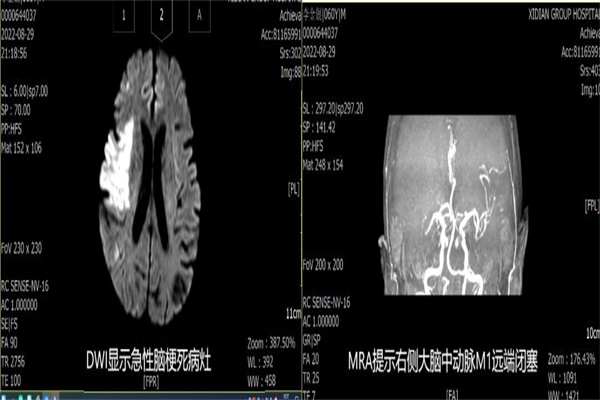

在將張爺爺送往西安途中,寧陜縣醫(yī)院值班醫(yī)生與西電集團(tuán)醫(yī)院急診科綠道值班醫(yī)生電話溝通病情。入院后,立即啟動(dòng)腦卒中綠色通道,在影像科、檢驗(yàn)科等多科室協(xié)作下,30分鐘內(nèi)完成急診化驗(yàn)、頭顱CT及MRI等檢查,神經(jīng)內(nèi)科介入團(tuán)隊(duì)根據(jù)檢查結(jié)果考慮張爺爺為急性腦梗死、右側(cè)大腦中動(dòng)脈閉塞,考慮心源性栓塞。

神經(jīng)內(nèi)科介入團(tuán)隊(duì)醫(yī)護(hù)人員迅速到位,穿刺過程順利。但由于張爺爺合并高血壓、糖尿病及長(zhǎng)期大量吸煙,動(dòng)脈硬化迂曲明顯而且是超級(jí)Ⅲ型弓,團(tuán)隊(duì)人員克服重重困難,順利將導(dǎo)絲導(dǎo)管到位,通過全腦血管造影術(shù)檢查,明確張爺爺右側(cè)大腦中動(dòng)脈閉塞。